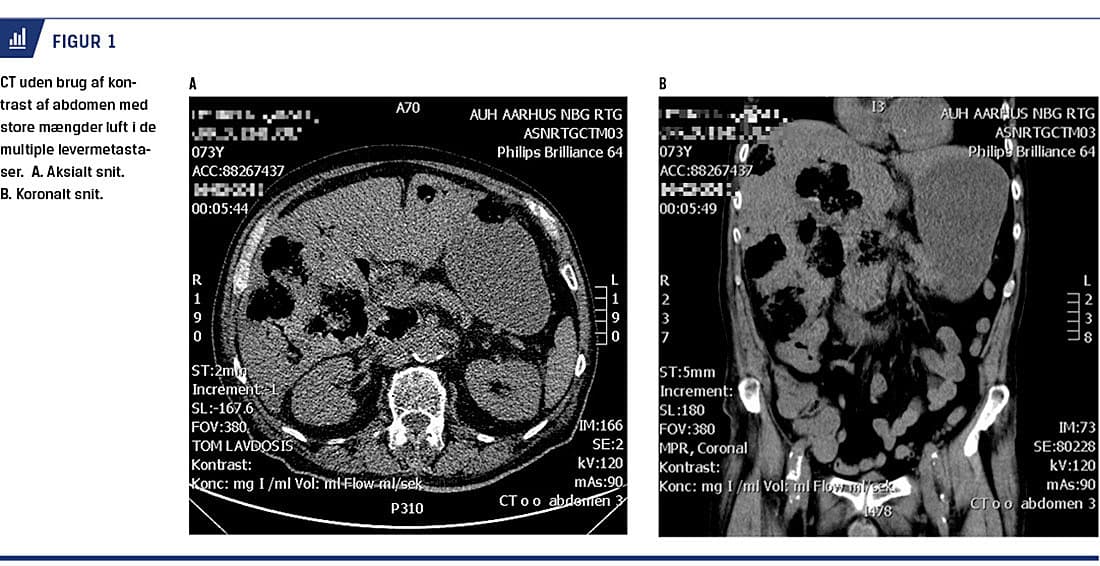

En 73-årig mand, hos hvem der netop var påbegyndt palliativ kemoterapi og epidermal vækstfaktor-receptor (EGFR)-hæmmer for levermetastaserende coloncancer, blev indlagt fire dage efter behandlingsstart med akutte mavesmerter og et døgns febrilia. Ved ankomsten var han respiratorisk påvirket med en respirationsfrekvens på 44 åndedrag pr. min og en saturation på 84% uden ilttilskud. Han var højfebril og takykard, men bleg og perifert kølig. Blodtrykket var initialt stabilt. Ved den objektive undersøgelse var der udtalt ømhed i øvre abdomen samt tiltagende peritoneal reaktion. En arterieblodgasanalyse viste massiv laktatophobning med et laktatniveau på 20 mmol/l, men normal pH-værdi pga. respiratorisk kompensation. Biokemisk var der C-reaktivt protein-niveau på 321 mg/l, men leukocytniveauet var inden for normalom rådet. På indikationen akut abdomen blev der foretaget en CT, som viste store mængder luft i de multiple levermetastaser samt luft i en retroperitoneal lymfeknudemetastase. Der var enkelte små luftbobler frit i peritoneum. Primærtumoren var uændret i forhold til tidligere (Figur 1A og B ).